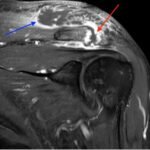

Septic arthritis of native joints is uncommon, but the condition can be threatening to life and limb if left untreated.1 Septic arthritis of the acromioclavicular (AC) joint of the shoulder is particularly rare and has only appeared sparsely in medical literature, mainly through individual case reports. Early recognition and treatment of the condition is vital, but diagnosis of septic AC arthritis can be difficult due to its presentation with vague symptoms and nonspecific laboratory findings. This case report describes the care of a patient with poorly managed diabetes who presented to the emergency department with one month of pain and swelling of the left shoulder and two weeks of pain and swelling in the right ankle. Imaging revealed fluid in the AC joint, and laboratory evaluation showed an elevation in inflammatory markers, including leukocyte count, C-reactive protein (CRP), and erythrocyte sedimentation rate (ESR). The patient’s hospital course was complicated by methicillin-sensitive Staphylococcus Aureus bacteremia without evidence of sepsis. The patient underwent open debridement and washout of both the ankle and AC joint without complication. After recovery, the patient was discharged to a rehabilitative center with IV antibiotics and weekly follow up care with infectious disease specialists. This case illustrates the importance of early diagnosis and treatment of septic arthritis, even in less common joint spaces, to prevent progression of this dangerous disease.